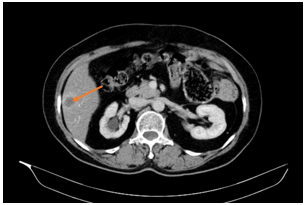

-        CLVT lồng ngực - ổ bụng:

Hình 1. Nhu mô gan phải có nốt ngấm thuốc kém chủ yếu ngấm viền ngoại vi đường kính ~ 25mm